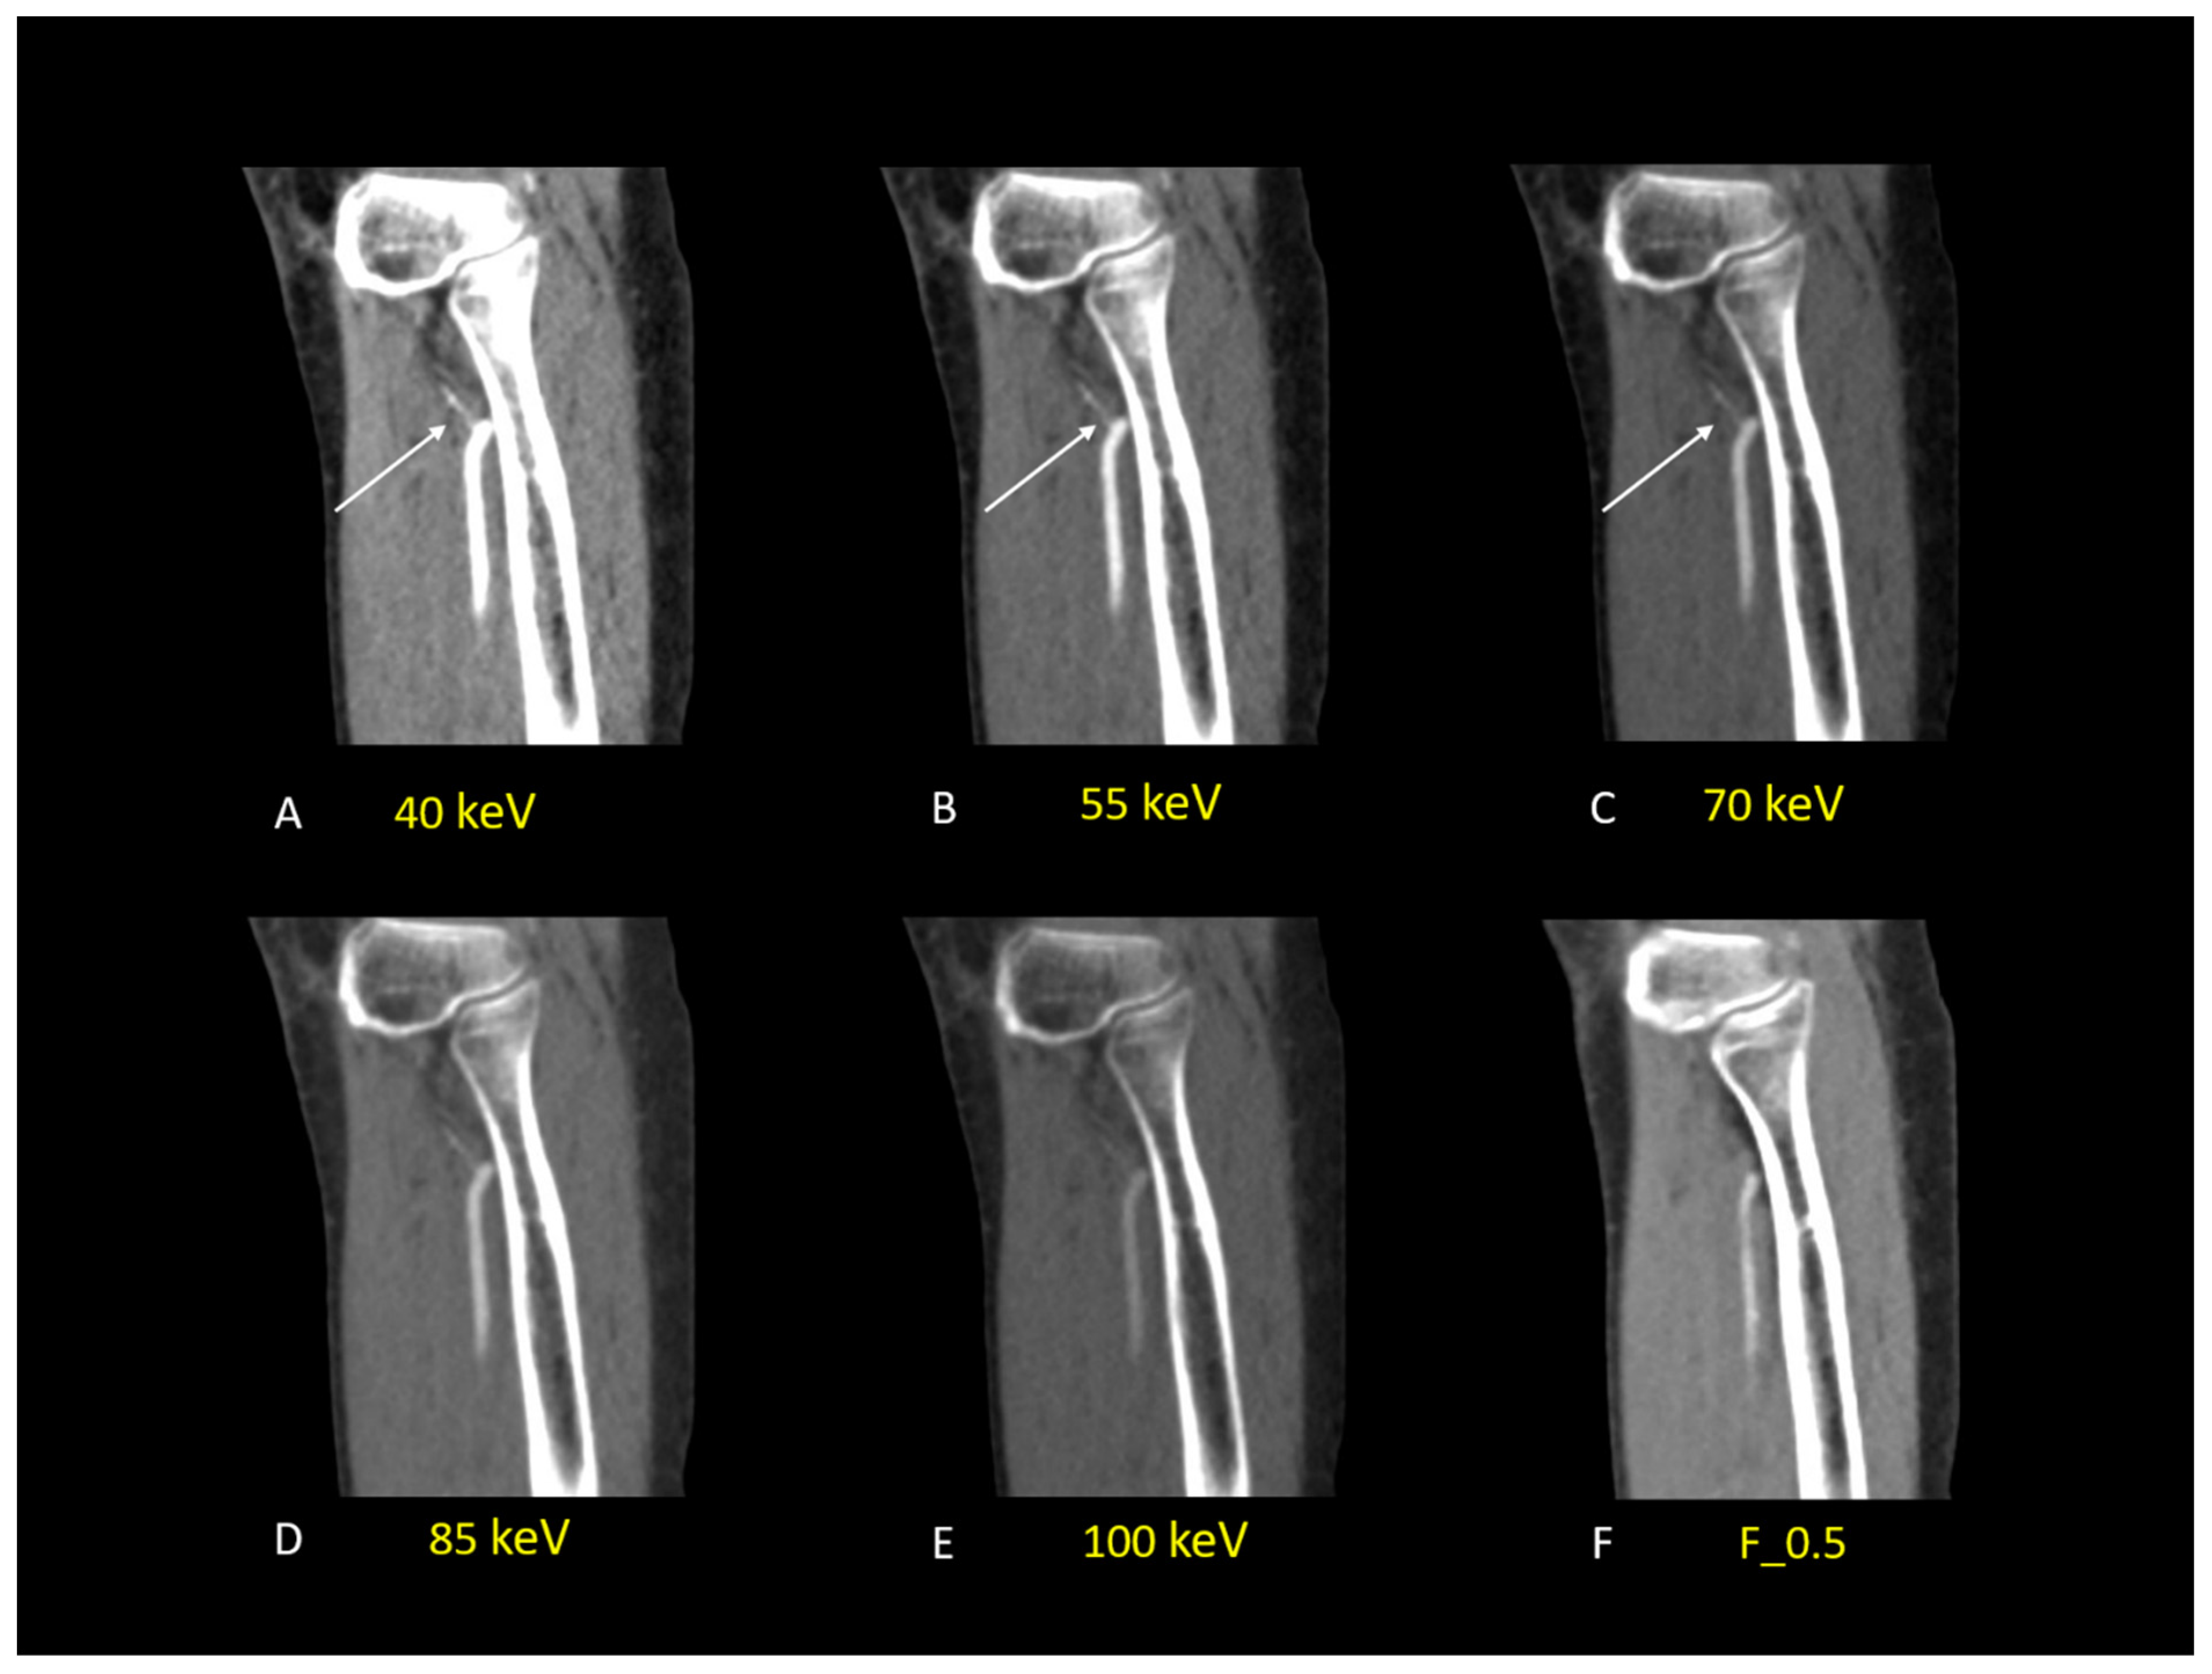

| Parameters | 40 keV | 55 keV | 70 keV | 85 keV | 100 keV | F_0.5 |

|---|---|---|---|---|---|---|

| Attenuations | ||||||

| ATA | 1174.97 ± 284.23 | 654.73 ± 145.84 | 407.39 ± 84.02 | 281.43 ± 53.06 | 210.85 ± 36.14 | 249.43 ± 29.08 |

| FA | 1138.28 ± 319.33 | 636.71 ± 171.39 | 391.74 ± 102.12 | 273.76 ± 64.78 | 205.94 ± 46.09 | 259.21 ± 31.21 |

| PTA | 1227.97 ± 254.92 | 681.01 ± 136.60 | 419.15 ± 80.77 | 285.62 ± 52.81 | 209.79 ± 35.89 | 245.33 ± 29.95 |

| Average all vessels | 1180.41 ± 45.09 | 657.48 ± 22.28 | 406.09 ± 13.75 | 280.27 ± 6.01 | 208.86 ± 2.58 | 251.32 ± 7.13 |

| Noise | 40.34 ± 5.72 | 28.97 ± 5.57 | 21.36 ± 4.60 | 19.64 ± 3.25 | 19.92 ± 2.99 | 20.75 ± 5.48 |